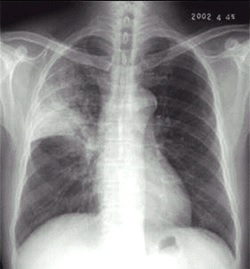

02卷-4.男性,24岁,发热、咳嗽、咳痰4天。诊断(本题满分2.00分)

A.右上肺不张

B.右上胸膜肥厚

C.右上肺癌

D.右上肺炎

本题答案:D

题目解析:【该题针对“X线-肺炎”知识点进行考核】